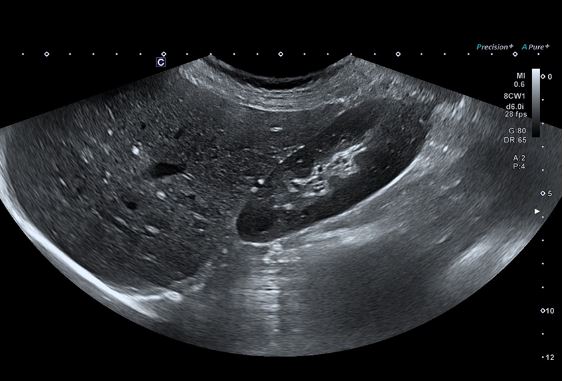

Клінічні зображення

Ультра широкий огляд печінки та нирок надає більше інформації в одній площині.

Технологія візуалізації мікропотоків (SMI) відображає кровотоки низької швидкості у нирці.

Конвексний датчик PVU-475BTW (8CW1)

Монокристалічний конвексний датчик забезпечує зображення високої роздільної здатності для абдомінальних досліджень. Висока щільність елементів у поєднанні з iBeam+ забезпечує ультрашироке поле огляду 140°, яке наразі доступне лише для Aplio i-серії.